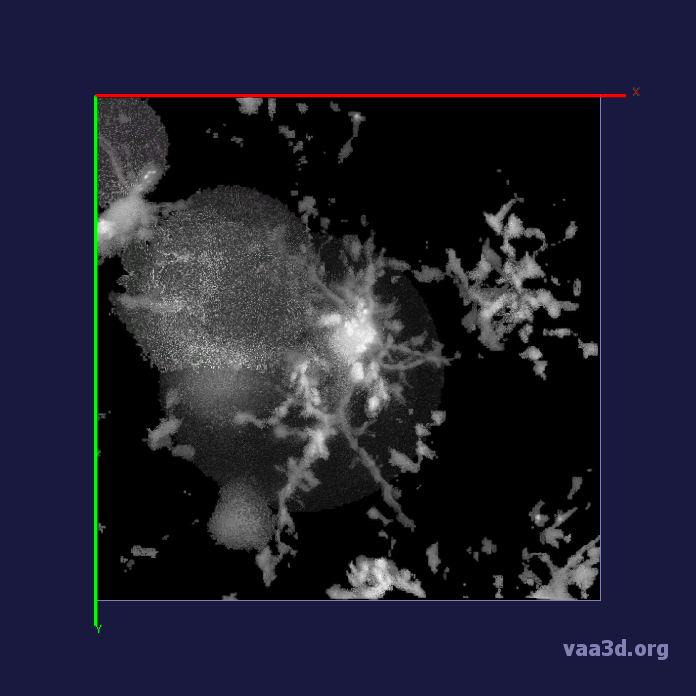

The 3D movies of microglia were imaged over 20 minutes with z-stacks taken at one minute intervals, containing single or multiple microglia per field of view. Some of the images were cropped from a larger field of view containing about 10 different cells and two images were imaged from a zoomed in view of one individual cell. The images ranged from a horizontal pixel width of .01 um and a vertical pixel width of .01 um to horizontal pixel width of .2 um and a vertical pixel width of .2 um. In the 3D images, there is variation in intensity contrast throughout the cell, non-structural noise, and fluorescence bleeding through z-stack due to the lengthy imaging technique which makes it difficult to visualize and process. The images were pre-processed using histogram equalization which increased the intensity throughout the cell but further increased noise in the background.

In our experiments, we compare the coupled TuFF-BFF microglia segmentation results with those given by L2S [21] and the Chan-Vese segmentation method [22]. The groundtruth in 3D was attained by manually tracing the object slice by slice from the z-stack. It must be noted that this was done by eye and could have some error. Figure 2 shows the visual comparison of the segmentation results for our dataset. Our result shown on the third column captures both the soma and processes. Figure 3 shows the Dice coefficient comparison of each segmentation method to the ground truth. Since the soma is much larger than the fine processes in the microglia, the processes have less volumetric impact on the similarity score. As explained in Section 1, segmenting the processes is important for quantifying the extension from the soma and its volume of surveillance. We use the Dice coefficient to quantitatively compare the ramification by taking the convex hull of the resulting segmentation. The Dice coefficient is a similarity measure that is computed using with where is the ground truth and is the compared image.

From Figure 4, the average Dice score for coupled TuFF-BFF was 0.77, compared to 0.53 for L2S [21] and .58 for Chan-Vese [22]. It must be noted that L2S required manual user initialization for each 2D image in the stack. While the Chan-Vese method has automatic seed selection, our coupled TuFF/BFF method was the only method that was a true 3D segmentation algorithm. L2S could not consistently capture the entire processes due to the intensity inhomogeneity throughout the object and background noise. The Chan-Vese segmentation could capture the extensions of the processes but did not work well with noise and attained false positives in the reconstruction. Since our method uses the tubular and blob information of the object to separate foreground and background, the segmentation only evolved within the object boundaries.